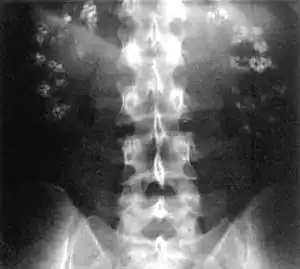

- Bone demineralisation (causing rickets in children and osteomalacia in adults

The principal feature of Fanconi syndrome is bone demineralization (osteomalacia or rickets) due to phosphate wasting.